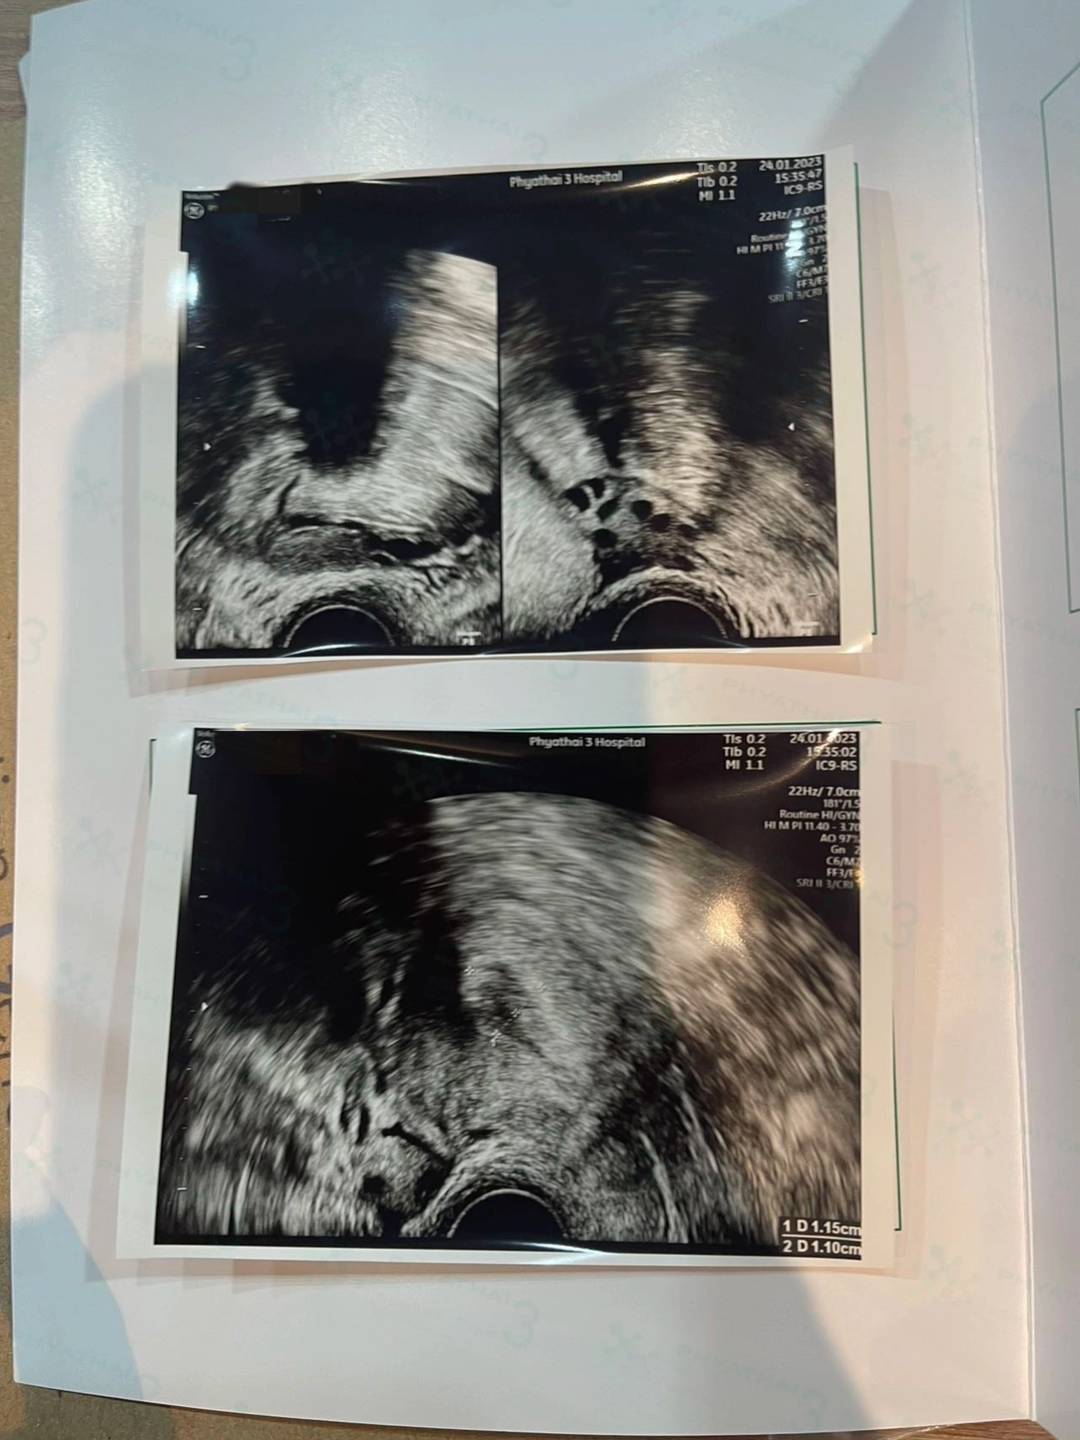

今天是我们患者来到泰国的第一次调理内膜的见诊了,今天看到姐妹的内膜也是对药效吸收比较好,内膜也超级漂亮,只是姐妹之前一直存在心里面的疑惑就势甲状腺和泌乳素,今天也已经处理好了,因为医生直接让我们上楼见诊专科医生会更加方便专业,等待明天的见诊结果噢,希望姐妹顺顺利利带宝宝回家